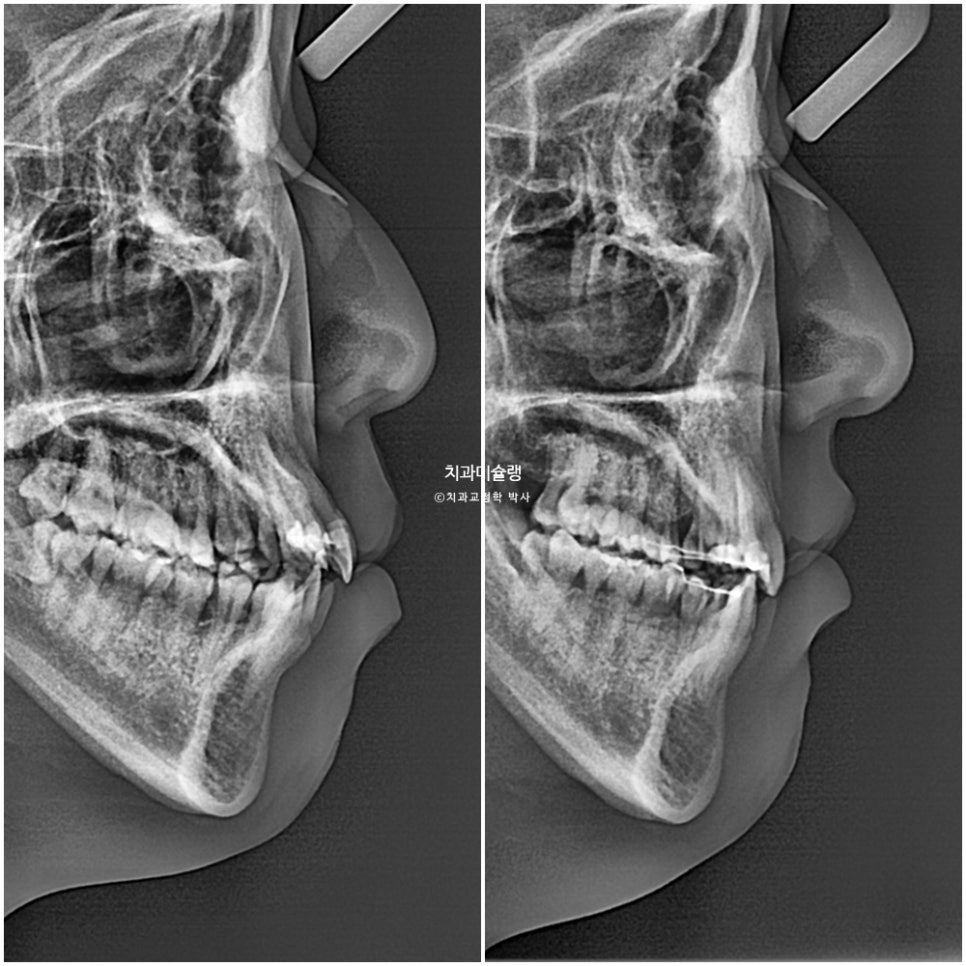

뻗치지도 옥니도 아닌 적절한 앞니 각도

돌출이 해소되며 입이 자연스럽게 다물리게 되었습니다.

치근흡수는 없으며 어금니 쓰러짐 없이 잘 마무리 되었습니다.

돌출감의 해소와 앞니 각도 변화는 전후 엑스레이에서 잘 보입니다.